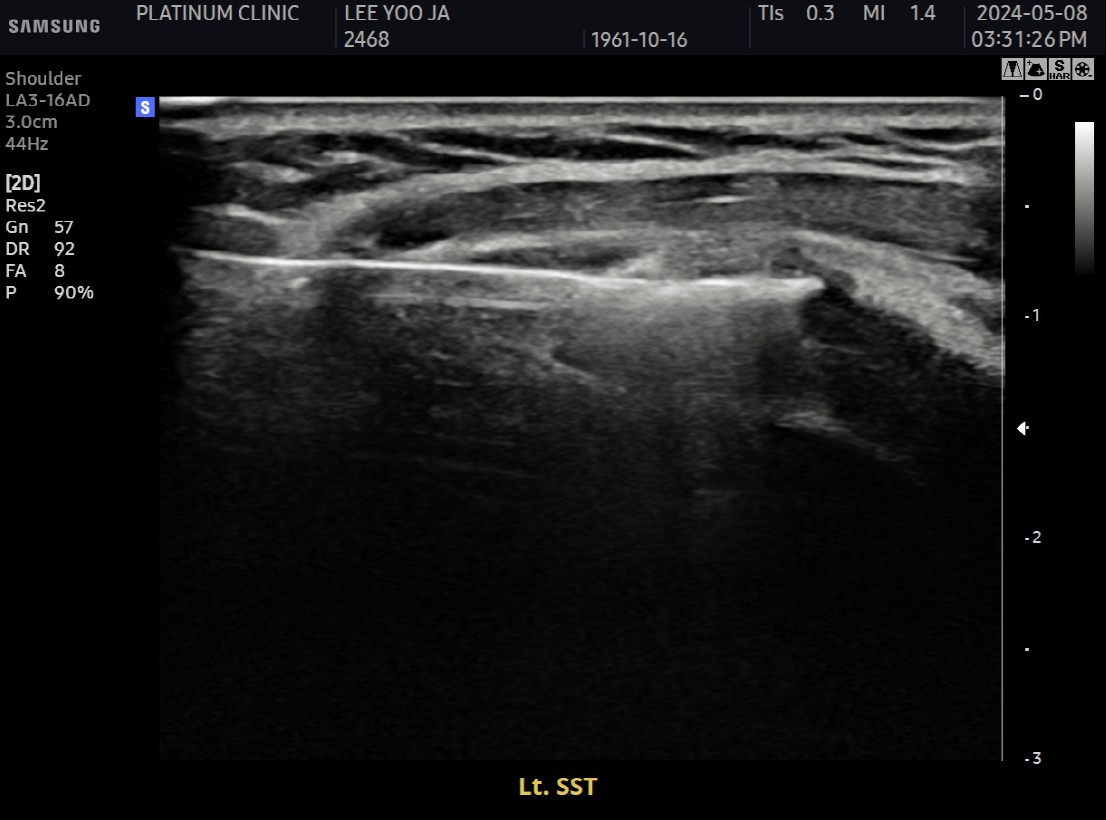

Step 2: 초음파 유도 하 가이드 삽입

초음파로 석회 위치를 실시간 확인하면서 특수 가이드를 삽입합니다.

피부에 작은 절개 (약 2~3mm)

가이드를 석회 바로 옆에 위치

인대를 관통하지 않고 석회에 직접 접근

Step 3: 석회 분쇄

전용 분쇄 기구를 가이드에 통해 삽입하여 석회를 분쇄합니다.

단단한 석회도 물리적으로 깨뜨림

초음파로 분쇄 과정 실시간 확인

석회가 잘게 부서지는 것이 보임

Step 6: 최종 확인 및 마무리

초음파와 X-ray로 석회 제거 확인 후 마무리합니다.

초음파: 석회 부위 확인

X-ray: 석회 완전 제거 확인